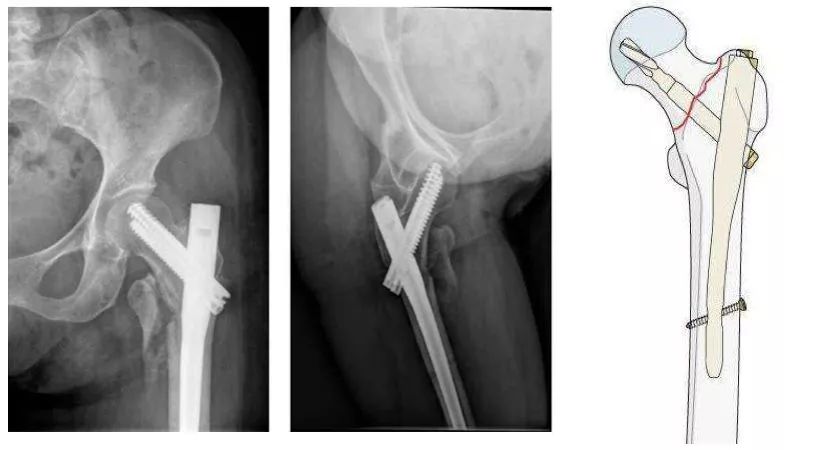

粗隆间骨折,骨质疏松,把持力不良,钉板固定,螺钉切割失败。